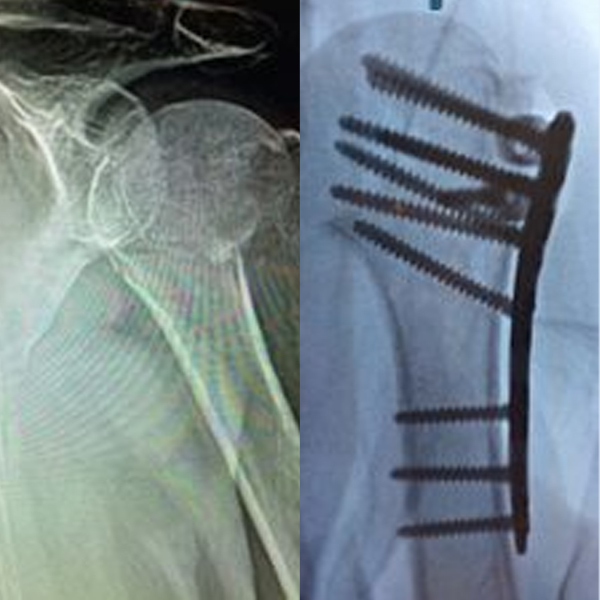

Cas1